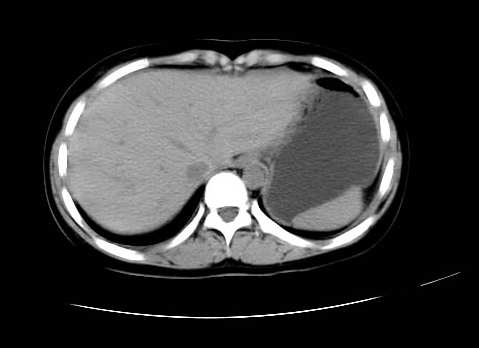

女 16岁  右上腹痛一天,无其他不适

肿块最大径位于十二指肠降段与水平段移行处,并且与肝脏压迹呈“0”形征,可以考虑位于肝外并与胃肠道关系紧密,考虑胃肠道间质瘤(gist)可能较大,须除外神经节起源肿瘤。

肿块与十二指肠关系密切,支持间质瘤诊断.肝脏与结肠均为受压改变.

右下腹巨大肿快,密度不均匀,内见坏死低密度区,边界清楚,与周边胀器明显有分界,未见强化,多考虑来源于间叶组织的良性肿物.

我坚决反对您的观点,该病例定位:横结肠肝曲与升结肠之间的肠系膜及部分肠壁。请看下图:

病灶巨大,少部分向肠腔内生长,大部分向长腔外生长。其密度不均匀,增强显示明显不均匀强化,并见有大片状始终不强化的不规则坏死液化区。虽然病灶中上部形态尚可,病人又如此年轻,但中下部形态、密度、强化特点强烈提示为恶性病灶。综上,我考虑本病例为:恶性胃肠道间质瘤。